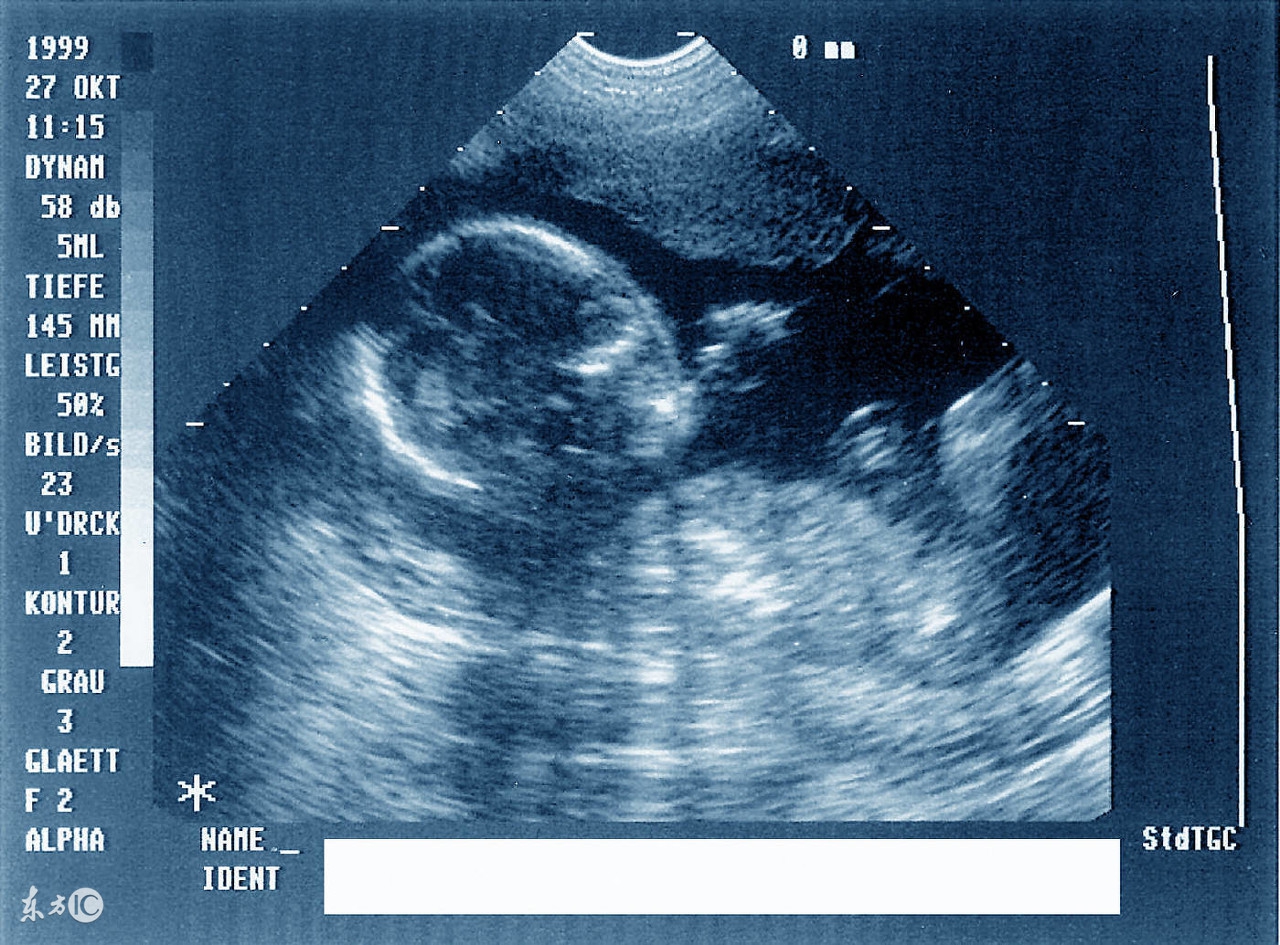

周力学介绍,这是目前国内外使用最广泛、最安全的胎儿影像学检查,可以观察胎儿大小、胎位、胎动、胎盘及羊水情况;还可以进行胎儿畸形筛查和血流动力学检测。随着科技的发展,当宝宝还未出世的时候,妈妈就可以通过三维和四维超声来观赏一下宝宝的小脸了。

周力学介绍说,第一次产前超声检查最好选择在停经六七周,选择经阴道彩超或者经腹部彩超,由于此时孕囊和宝宝较小,阴道超声下可能显示会更清晰。此时宫腔内已经可以看到妊娠囊,妊娠囊内可以看到胚芽,也就是宝宝早期的形态,如果位置好的话还看得见宝宝原始心管搏动。

早期产前超声发现了有心管搏动的胚芽后,准妈妈们可以准备预约第二次产前超声(孕13+6周III级彩超检查)了,这次时间位于停经11-13+6周。早期,这项检查的出现主要通过测量宝宝颈项透明层(也就是大家听得比较多的NT)和胎儿鼻骨来进行宝宝染色体疾病的筛查。目前这项检查也包含早期胎儿畸形的筛查及诊断,例如无脑儿、联体双胎、露脑畸形、各种常见的胎儿心脏畸形、肾脏缺如等。

完成了13+周产前III级彩超检查,又过了一个关卡的准妈妈们可以开始预约第三次产前超声(中孕产前III级彩超检查)了,也就是俗称的大排畸,也是很多准妈妈心心念念的三维检查。这项检查一般合适时机位于18周-24周。太小了宝宝还没发育好,检查价值不能完全达到,太晚了宝宝又比较大了,有的位置看得不太好,最佳时间一般位于21周-24周。这个阶段由于宝宝大部分器官已经发育,结构也比较清晰,可以进行的大部分器官结构筛查,可以排除大部分复杂胎儿畸形。

第四次和第五次产前超声检查最好安排在32-36周,选择I级或者II级产前超声检查。可以了解胎儿大小、位置、胎盘位置和成熟度、羊水量等,这些对于准妈妈们选择与宝宝见面的方式和时间有着重要的指导意义。